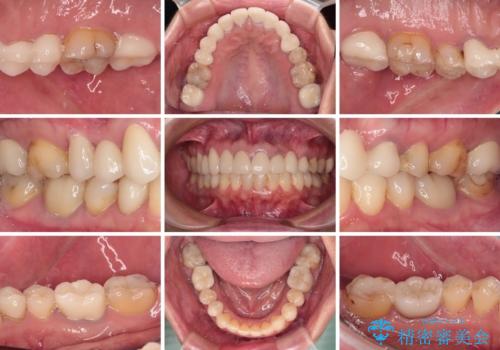

欠損やむし歯の歯をきれいなセラミックに 全顎虫歯治療

- 他院で矯正治療を終えたものの、むし歯や欠損部の治療が進められないとのことで来院された患者様です。

欠損部や、銀歯やむし歯の大きな歯はセラミッククラウンやブリッジに、小さいむし歯はセラミックインレーにて治療を行うこととしました。